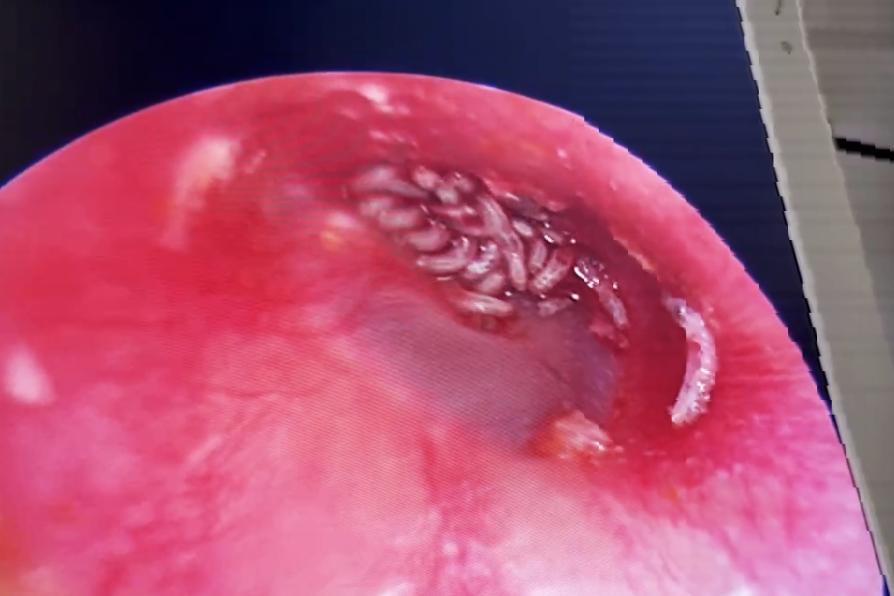

Tiến hành nội soi lỗ tai của người phụ nữ ở TPHCM, các bác sĩ kinh hãi phát hiện gần 20 con giòi bò lúc nhúc bên trong, khiến bệnh nhân chịu nhiều đau đớn.

Tại Bệnh viện Lê Văn Thịnh, người phụ nữ được chỉ định nội soi lỗ tai kiểm tra. Quá trình nội soi, các bác sĩ không khỏi bất ngờ và kinh hãi khi phát hiện đang bò lúc nhúc bên trong.

Sau đó, các bác sĩ xịt oxy già vào trong để tiến hành hút giòi, đồng thời vệ sinh ống tai cho bệnh nhân. Đến khi làm sạch hết ổ giòi trên, các bác sĩ đếm được tổng cộng gần 20 con. Bệnh nhân sau đó được kê toa thuốc và cho xuất viện, hẹn tái khám phòng trường hợp còn sót giòi trong tai.

Theo bác sĩ Hùng, bệnh nhân trên có thể đã bị một con côn trùng nào đó bay vào tai, sau đó đẻ trứng bên trong. Trứng theo thời gian sinh trưởng đã nở ra thành ấu trùng giòi. Đây cũng là lần đầu tiên khoa Tai mũi họng, Bệnh viện Lê Văn Thịnh tiếp nhận bệnh nhân có nhiều giòi sống trong lỗ tai.